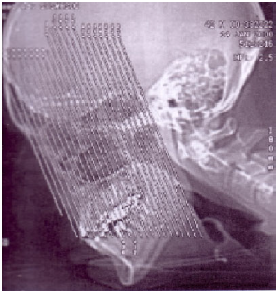

Com relação ao estudo tomográfico das cavidades paranasais, observe as imagens:

Baseado no topograma (scout) demonstrado acima, pode-se afirmar que os cortes serão obtidos no plano